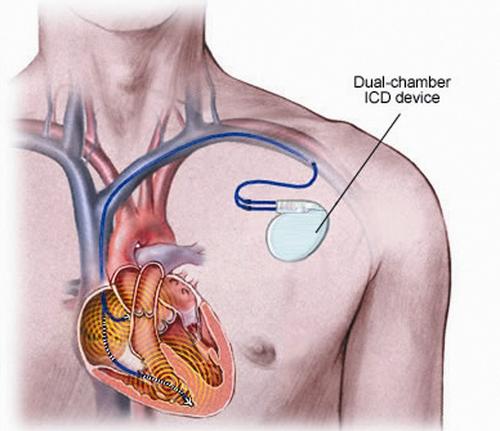

李主任指出,肥厚型心肌病是一种遗传性心肌病,以心室非对称性肥厚为解剖特点,是青少年运动猝死的最主要原因之一 。病因找到了,那怎么治疗呢?李主任指出,患者心肌已经肥厚,且肥厚型心肌病是一种遗传性疾病,药物很难逆转心肌肥厚,但患者已出现室颤、心跳骤停,猝死风险很高,为了减低患者猝死风险,可为患者植入体内自动除颤仪,一旦患者出现室颤,体内除颤仪能够立马识别,并自动除颤,保证患者生命安全,且此手术为微创手术,将体内除颤仪植于皮下,安全系数高,患者可耐受。准备就绪后,3月17日,李主任再次带领团队为黄先生行体内自动除颤仪植入术(ICD),并将ICD程控。